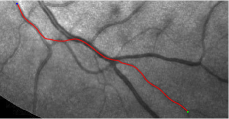

Compare to existing minimal path models. The Riemannian metrics used in [1, 4, 5] are based on the local pointwise information. The curvature-penalized metric [7, 6] and the proposed coherence-penalized metric are able to consider more constraints, i.e., the rigidity for [7, 6] and feature coherence for our metric. These constraints are beneficial to the respective geodesics to reduce the risk of short branches combination problem. Compared to the curvature-penalized metric, our method can be more flexible since the feature map can be produced dependently on the task. In retinal imaging, veins and arteries are distinguishable in terms of gray levels or vesselness values, satisfying the formulation of the proposed model. Especially for vessels with strong tortuosity, the curvature-penalized metric, which favours a smooth curve, fails to catch the expected vessels as shown in the left column of Fig. 2. From the right column of Fig. 2, one can see that our model can obtain a good result.

Validation. We validate our minimal path model on respective 54 and 30 patches obtained from the DRIVE [14, 15] and the IOSTAR [16] datasets with AV groundtruth. Each artery involved in these parches locates near a vein or crossing it at least once. Our goal is to extract the artery between two given points. In order to get the quantitative evaluation, we first convert each continuous spatial path to an 4-connected digital path which is considered as a pixel collection. We denote by the collection of digital path pixels inside the artery groundtruth map . Thus, a measure can be simply defined as , where and mean the respective number of elements involved in and . We compare our model to four existing minimal path models: the isotropic Riemannian (IR) model [1], the anisotropic radius-lifted Riemannian (ArR) model [4], the isotropic orientation-lifted Riemannian (IoR) model [5] and the curvature-penalized (CuP) model [7]. The construction of these metrics are based on the OOF outputs [12]. Note that a centerline-based potential is chosen so that we remove the radius dimension of [5] to reduce computation complexity. The results in terms of the score are presented in Table 1, including the average (Avg.), maximum (Max.), minimum (Min.) and standard deviation (Std.) values. In both DRIVE and IOSTAR datasets, our method can achieve the best performances thanks to the coherence penalization. Note that in Table 1, we evaluate our method by using the refined paths instead of using the original coherence-penalized minimal paths. For comparisons in visualization, we show the minimal paths from the ArR metric , the CuP metric and the proposed coherence-penalized metric on three retinal patches as shown in Fig. 3. The targeted artery vessels which cross veins at least once are labeled by red color in column 1. The paths shown in column 4 from the proposed metric are results after refinement. One can claim that our method indeed can catch expected arteries while other metrics fall into the traps of short branches combination.